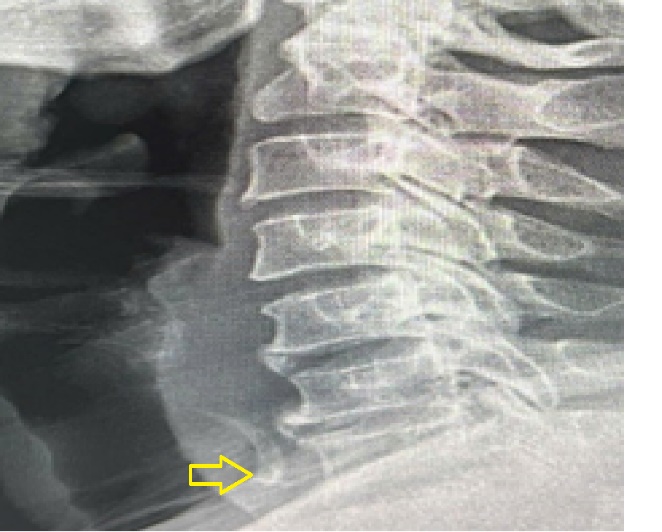

Hình ảnh dị vật trên phim X-quang